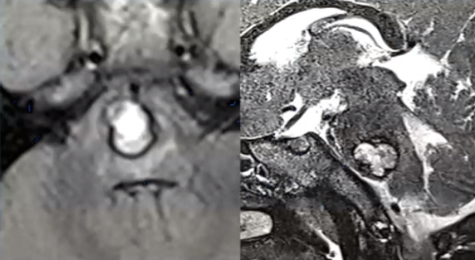

经检查确诊男孩患有海绵状血管瘤。虽然该病变属良性性质,但可能引发脑干出血,导致瘫痪、功能永久性损伤甚至死亡等严重并发症。然而病情恶化速度超出预期。

原本活动正常的男孩突发脑干出血,出现剧烈头痛、左侧肢体瘫痪及右眼活动受限等症状。直至术前阶段,患儿持续处于意识障碍状态,即使在气管插管操作时仍未睁眼。